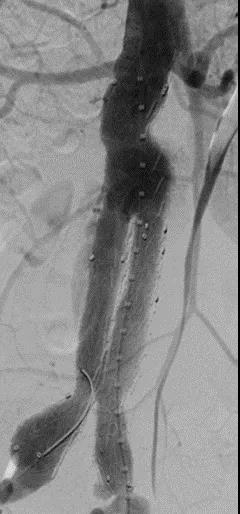

此次研究,纳入腹主动脉瘤的最大直径为85mm,平均直径为50.78mm;最短瘤颈长度为11mm,平均长度为31.34mm;最大肾下成角为74.6度,平均角度为32.48度。从动脉瘤最大直径变化来看,经过腹主动脉腔内治疗后,在出院前和术后6个月都有所减小。 在此次研究中,先健Yuranos™新一代腹主动脉覆膜支架系统临床试验初步展现了优秀的临床试验结果,其30天内MAE发生率低,安全性得以验证;而且由于该产品的柔顺性有较大提升,输送器直径减小,对于短瘤颈和角度大的病例是更好的选择。 入组病例展示: 病例一:男性,年龄69岁,既往高血压,糖尿病病史。术前腹主动脉瘤直径67.3mm,近端瘤颈长度23.2mm,近端锚定区直径21.2mm,肾下成角60.5度。 术中从右侧股动脉穿刺,选用先健型号为AB-2412-50-120的主体支架,支架近端定位于右肾动脉开口处,后释放打开裸支架,并向下释放主体短分支,左侧输送进入先健髂动脉延长支架IE-1416-100,并释放,保留左侧髂内动脉。接着释放主体长分支,右侧输送进入先健髂动脉延长支架IE-1424-80,并释放,保留右侧髂内动脉。 手术顺利,无内漏,持续时间1小时10分钟。术后CTA检查,支架形态良好,无内漏。详见下图: 术前影像 术中影像 出院前影像 术后6个月影像 术后1年影像 病例二:女性,年龄72岁,既往高血压,静脉曲张病史。术前腹主动脉瘤直径48.81mm,近端瘤颈长度16.15mm,近端锚定区直径18.43mm,肾下成角66度。 术中从右侧股动脉穿刺,选用先健型号为AB-2412-50-140的主体支架,支架近端定位于右肾动脉开口处,后释放打开裸支架,并向下释放主体短分支,左侧输送进入先健髂动脉延长支架IE-1414-120,并释放,保留左侧髂内动脉。接着释放主体长分支,右侧输送进入先健髂动脉延长支架IE-1414-80,并释放,保留右侧髂内动脉。